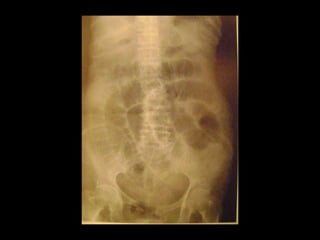

Colecistite Enfisematosa

Variante pouco comum da colecistite aguda;

Acredita-se que o comprometimento vascular da

artéria cística desempenhe algum papel no

desenvolvimento dessa condição, com proliferação

de microorganismos formadores de gás em

ambiente anaeróbico e penetração do gás na

parede da vesícula biliar;

Os organismos isolados são geralmente Clostridium

perfringens e Escherichia coli.

A TC é mais sensível e específica que a US e o RX

simples.

Colecistite Enfisematosa Variante pouco comum da colecistite aguda; Acredita-se que o comprometimento vascular da artéria cística desempenhe algum papel no desenvolvimento dessa condição, com proliferação de microorganismos formadores de gás em ambiente anaeróbico e penetração do gás na parede da vesícula biliar; Os organismos isolados são geralmente Clostridium perfringens e Escherichia coli.

Colecistite Enfisematosa Na revisãoda patologia dessa doença, as vesículas biliares com colecistite enfisematosa apresentaram uma incidência maior de endarterite obliterante. A taxa de mortalidade é de 15%, enquanto a colecistite aguda não complicada é de 4%. No caso de colecistite enfisematosa, é necessária uma intervenção cirúrgica imediata. A TC é mais sensível e específica que a US e o RX simples.